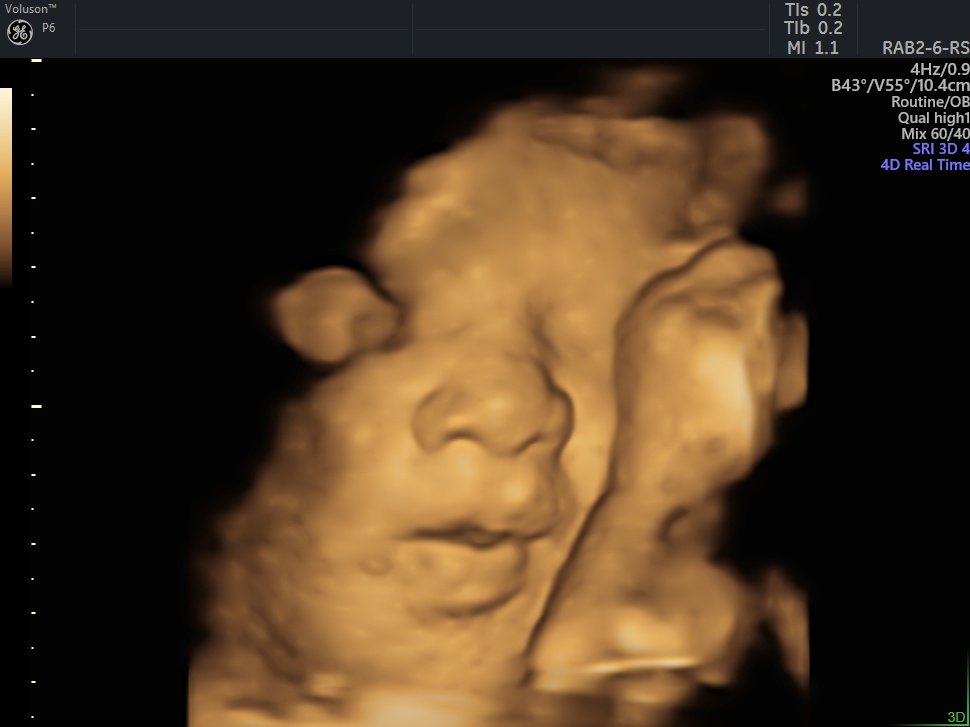

4 D Ultrasonografi

4 Boyutlu (Renkli) Ultrason ve Doppler Ultrasonografi